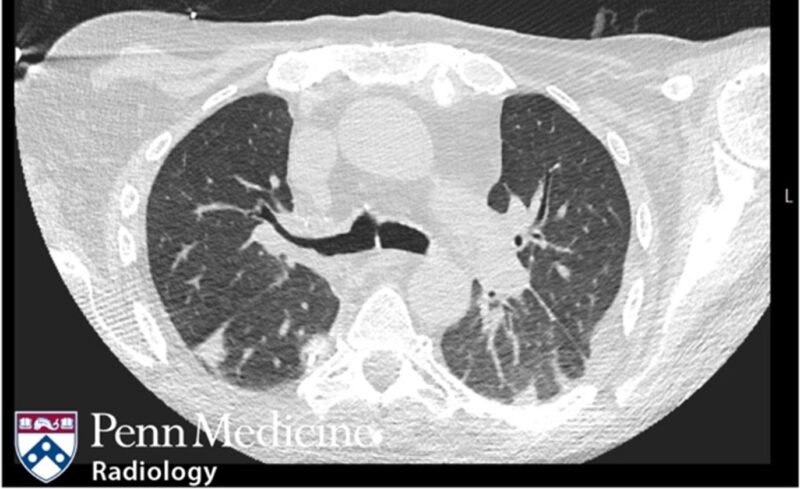

26-year-old man with neutropenia and dyspnea

A 26-year-old man with a history of familial nonischemic cardiomyopathy with heart transplantation presented with dyspnea on exertion and neutropenia.

Published Date: March 3, 2026